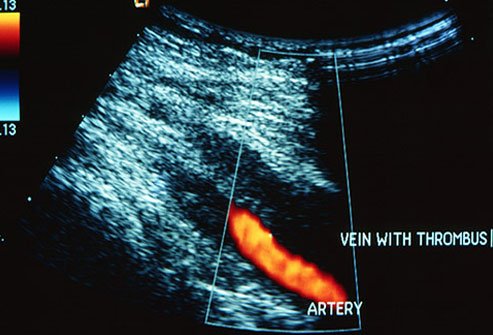

Get a Diagnosis

Your doctor will check you for signs of DVT. He may also ask about your medical history, medications you're taking, medical problems of close relatives, and things that raise your chances of having this condition. An ultrasound is the most common way to confirm you have it. The test uses sound waves to "see" the blood flow and reveal a clot. You might also need other tests, such as a blood test called a d-dimer.